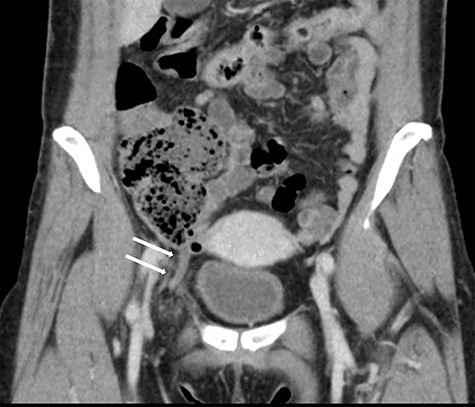

A 49-year-old woman presented to the emergency department with a 2-day history of a painful lump in the right groin. The patient did not complain fever, nausea, vomiting or a change in the bowel habits. Her medical history included pneumonia and chronic gastritis. Her general and nutritional status was good. Physical examination revealed a lump with local tenderness in the right groin below the inguinal region. There were no symptoms of dermatitis or peritonitis. Laboratory data revealed mild inflammation (white blood cells: 10 600/μl, C-reactive protein: 0.03 mg/dl). Abdominal CT revealed a blind-ended structure without an abscess inside the femoral canal. The mass was identified as a de Garengeot hernia (Fig. 1). Thereafter, an emergency surgery was scheduled; as CT did not reveal any signs of perforation, a one-stage laparoscopic procedure with a TEP-first approach was performed.

Coronal view in the abdominal CT scan shows the appendix inside the right femoral canal.